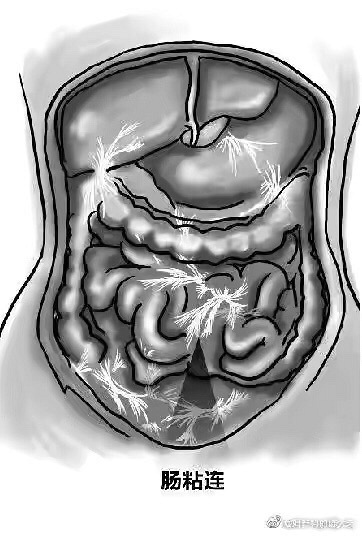

转自妇产科的陈大夫谈到剖腹产的话题,我觉得有必要再给大家看看这篇科普——关于如何预防剖宫产后盆腹腔粘连。很重要,还没生满两个娃的姐妹都应该要看看,万一呢? 盆腹腔手术以后的粘连会不会影响生活质量主要看运气。运气好,粘连的位置比较高,粘在小肠上,一般对生活质量不会有多少影响,如果后续不做手术,可能一辈子不会被发现。 但如果粘连的位置比较低,粘在乙状结肠和直肠上,那日子就没那么好过了。我曾遇到过一个疤